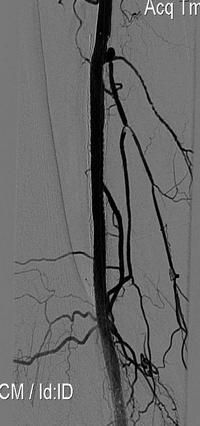

Произведена реканализация правой подколенной артерии и правого ТПС внутри ранее имплантированных стентов гидрофильным проводником, затем ЧБА с использованием баллона Opta Pro 4 x 40 mm с повторным стентированием стентами Smart и постдилатацией Opta Pro 6 x 60mm.